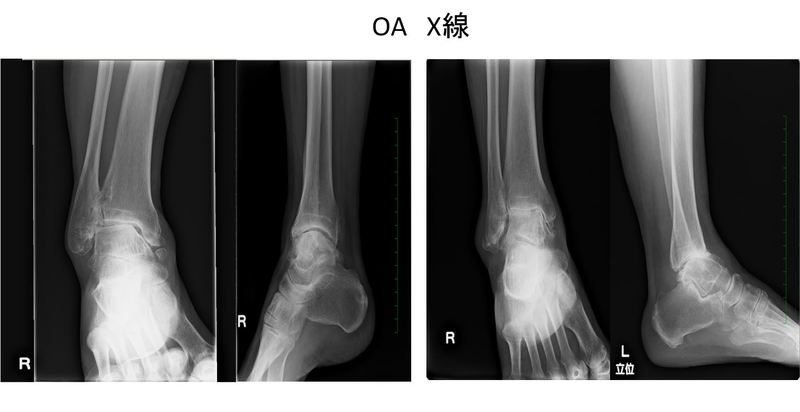

変形性足関節症が疑われる場合、一般的にはまずレントゲン検査を行います。レントゲン検査では関節の隙間の狭さ、骨棘(こつきょく)の有無、全体的な骨の位置関係や並び方(アライメント)をみることができます。

CT検査(コンピューター断層撮影法)は、レントゲン検査に次いで利用されます。コンピューター上で三次元の画像を作り出すこともでき(3D―CT)、骨棘や痛みの出ている箇所などが一目で確認できる検査です。